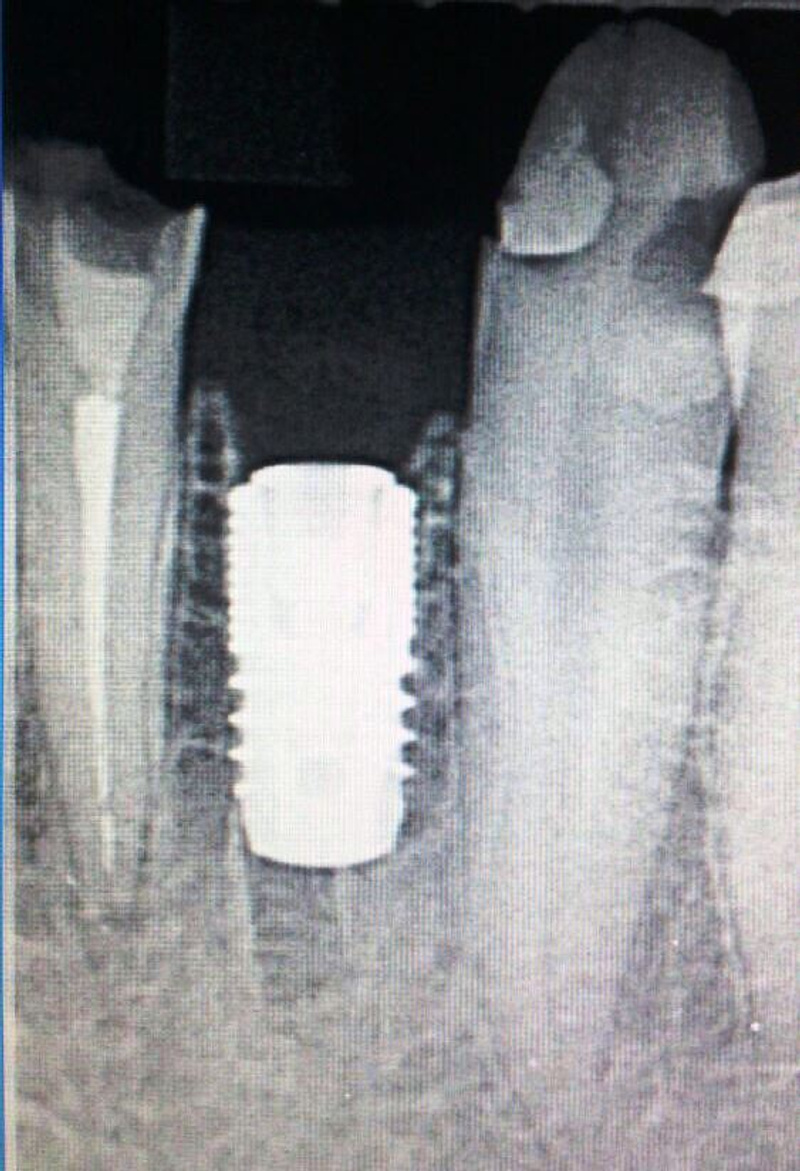

• Удаление+ имплантация.

Фронт. Удаление + Конмет(Россия).

Бок. отдел. Удаление+Implant Direct (USA).

Левый крайний диаметр 7.0 мм,для использования одномоментно в лунку моляра.

• Фронт.

• Бок. отдел.